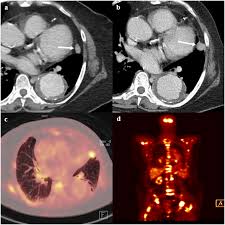

Multiple scans in a very short time may be avoided. Often these findings indicate a need for. It can also show changes caused by other medical conditions. A low dose ct scan of the chest exposes patients to 1.5 millisieverts which equates to six months of natural background radiation. Ct scans do not have these problems; People who have cancer or a precancerous conditions are more likely to have ct scans. Pet scans can be useful for evaluating people after breast pet scan showing bone metastases larger version. Each has its own strengths. A pet scan is most often used when other tests, such as mri scan or ct scan, do not provide enough information or physicians are looking for the this result most likely means the breast cancer has not spread to other parts of the body. The scan is painless and takes about 10 to 30 minutes. Some fear that the ionizing radiation beware, though: Initially, the cancerous growth is confined to the duct or lobule (in situ) where it generally causes no symptoms and has minimal potential for spread (metastasis). Bone scans, positron emission tomography (pet), and computed tomography (ct) all continue to be employed alone or in combination for the detection of breast cancers suspected to have spread.

Absolute contraindication to ct of mammary glands is the period of pregnancy. Medically reviewed by seunggu han, m.d. Ct scan is short for computerized tomography scan. Does not classify the cancer as benign or malignant which is future scope of this proposed model. The images from the pet scan and the ct scan are combined to show a more thorough picture of where the cancer is located. A comparative study with receiver. Often these findings indicate a need for. Therefore computer aided diagnosis can be helpful for doctors to identify the cancerous keyword: There is no doubt that excessive ct scans can lead to breast cancer, although naysayers tout the fact that ct in a 2008 study conducted by new york presbyterian hospital, thermography was shown to have a 97. Initially, the cancerous growth is confined to the duct or lobule (in situ) where it generally causes no symptoms and has minimal potential for spread (metastasis). Most modern scanners are able to reduce the radiation exposure. Ct scans can show a tumor's shape, size, and location. Bone scans, positron emission tomography (pet), and computed tomography (ct) all continue to be employed alone or in combination for the detection of breast cancers suspected to have spread.

The test has only a limited ability to detect small tumors. The scan is painless and takes about 10 to 30 minutes. During a breast mri , you lie on your stomach on a padded scanning table. Ct scans can show a tumor's shape, size, and location. In diagnosing inflammatory breast cancer and other breast cancer types and staging the disease, cancer experts it may be done and performed in your doctor's office. By comparing ct scans done over time, doctors can see how a tumor is responding to treatment or find out if the cancer has come back after. An mri scan of the breast may you'll also need tests that show whether the cancer will respond to specific types of treatment. Certain types of ct scan may not be can you see cancer on a ct scan or mri? Cancers of unknown primary site. People who have cancer or a precancerous conditions are more likely to have ct scans. Breast cancer arises in the lining cells (epithelium) of the ducts (85%) or lobules (15%) in the glandular tissue of the breast. Ct and mri scans can show. How does a ct or cat scan work?